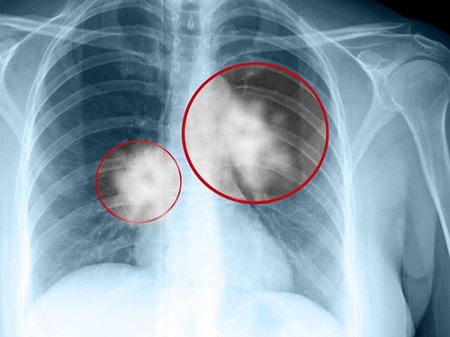

Ung thư phổi là một trong những căn bệnh nguy hiểm đang có nguy cơ tăng cao với tỷ lệ tử vong đáng báo động. Trong đó, có 4 nhóm nghề nghiệp dễ mắc bệnh này nhất, hãy cảnh giác để phòng tránh sớm.

Theo các chuyên gia y tế, bệnh ung thư phổi là một trong những bệnh lý ác tính phổ biến nhất, và là nguyên nhân tử vong hàng đầu ở độ tuổi trên 40 tại các quốc gia trên thế giới, trong đó có Việt Nam.

Ung thư phổi và những dấu hiệu nhận biết?

Ở giai đoạn sớm, bệnh thường không biểu hiện rõ ra bên ngoài. Tuy nhiên, khi bệnh phát triển, thường có các triệu chứng sau:

Đau tức ngực kéo dài, cố định ở cùng một vị trí.

Ho dai dẳng với tình trạng ngày một nặng, có thể ho ra máu.

Khó thở do khối u phát triển chèn ép lên đường hô hấp.